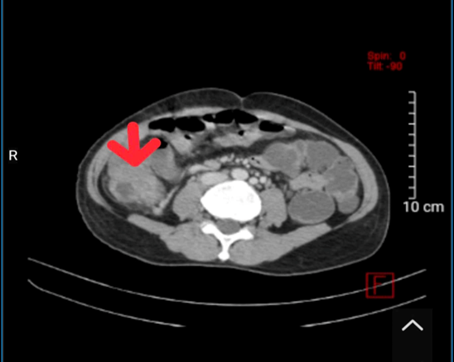

• Nội soi đại tràng toàn bộ:

• Hình 1: Hình ảnh nội soi đại tràng cho thấy tại vị trí đại tràng sigma có khối sùi loét, chiếm gần hết chu vi lòng đại tràng, máy soi không đi tiếp được.

• Chẩn đoán mô bệnh học trước mổ: ung thư biểu mô tuyến kém biệt hoá.